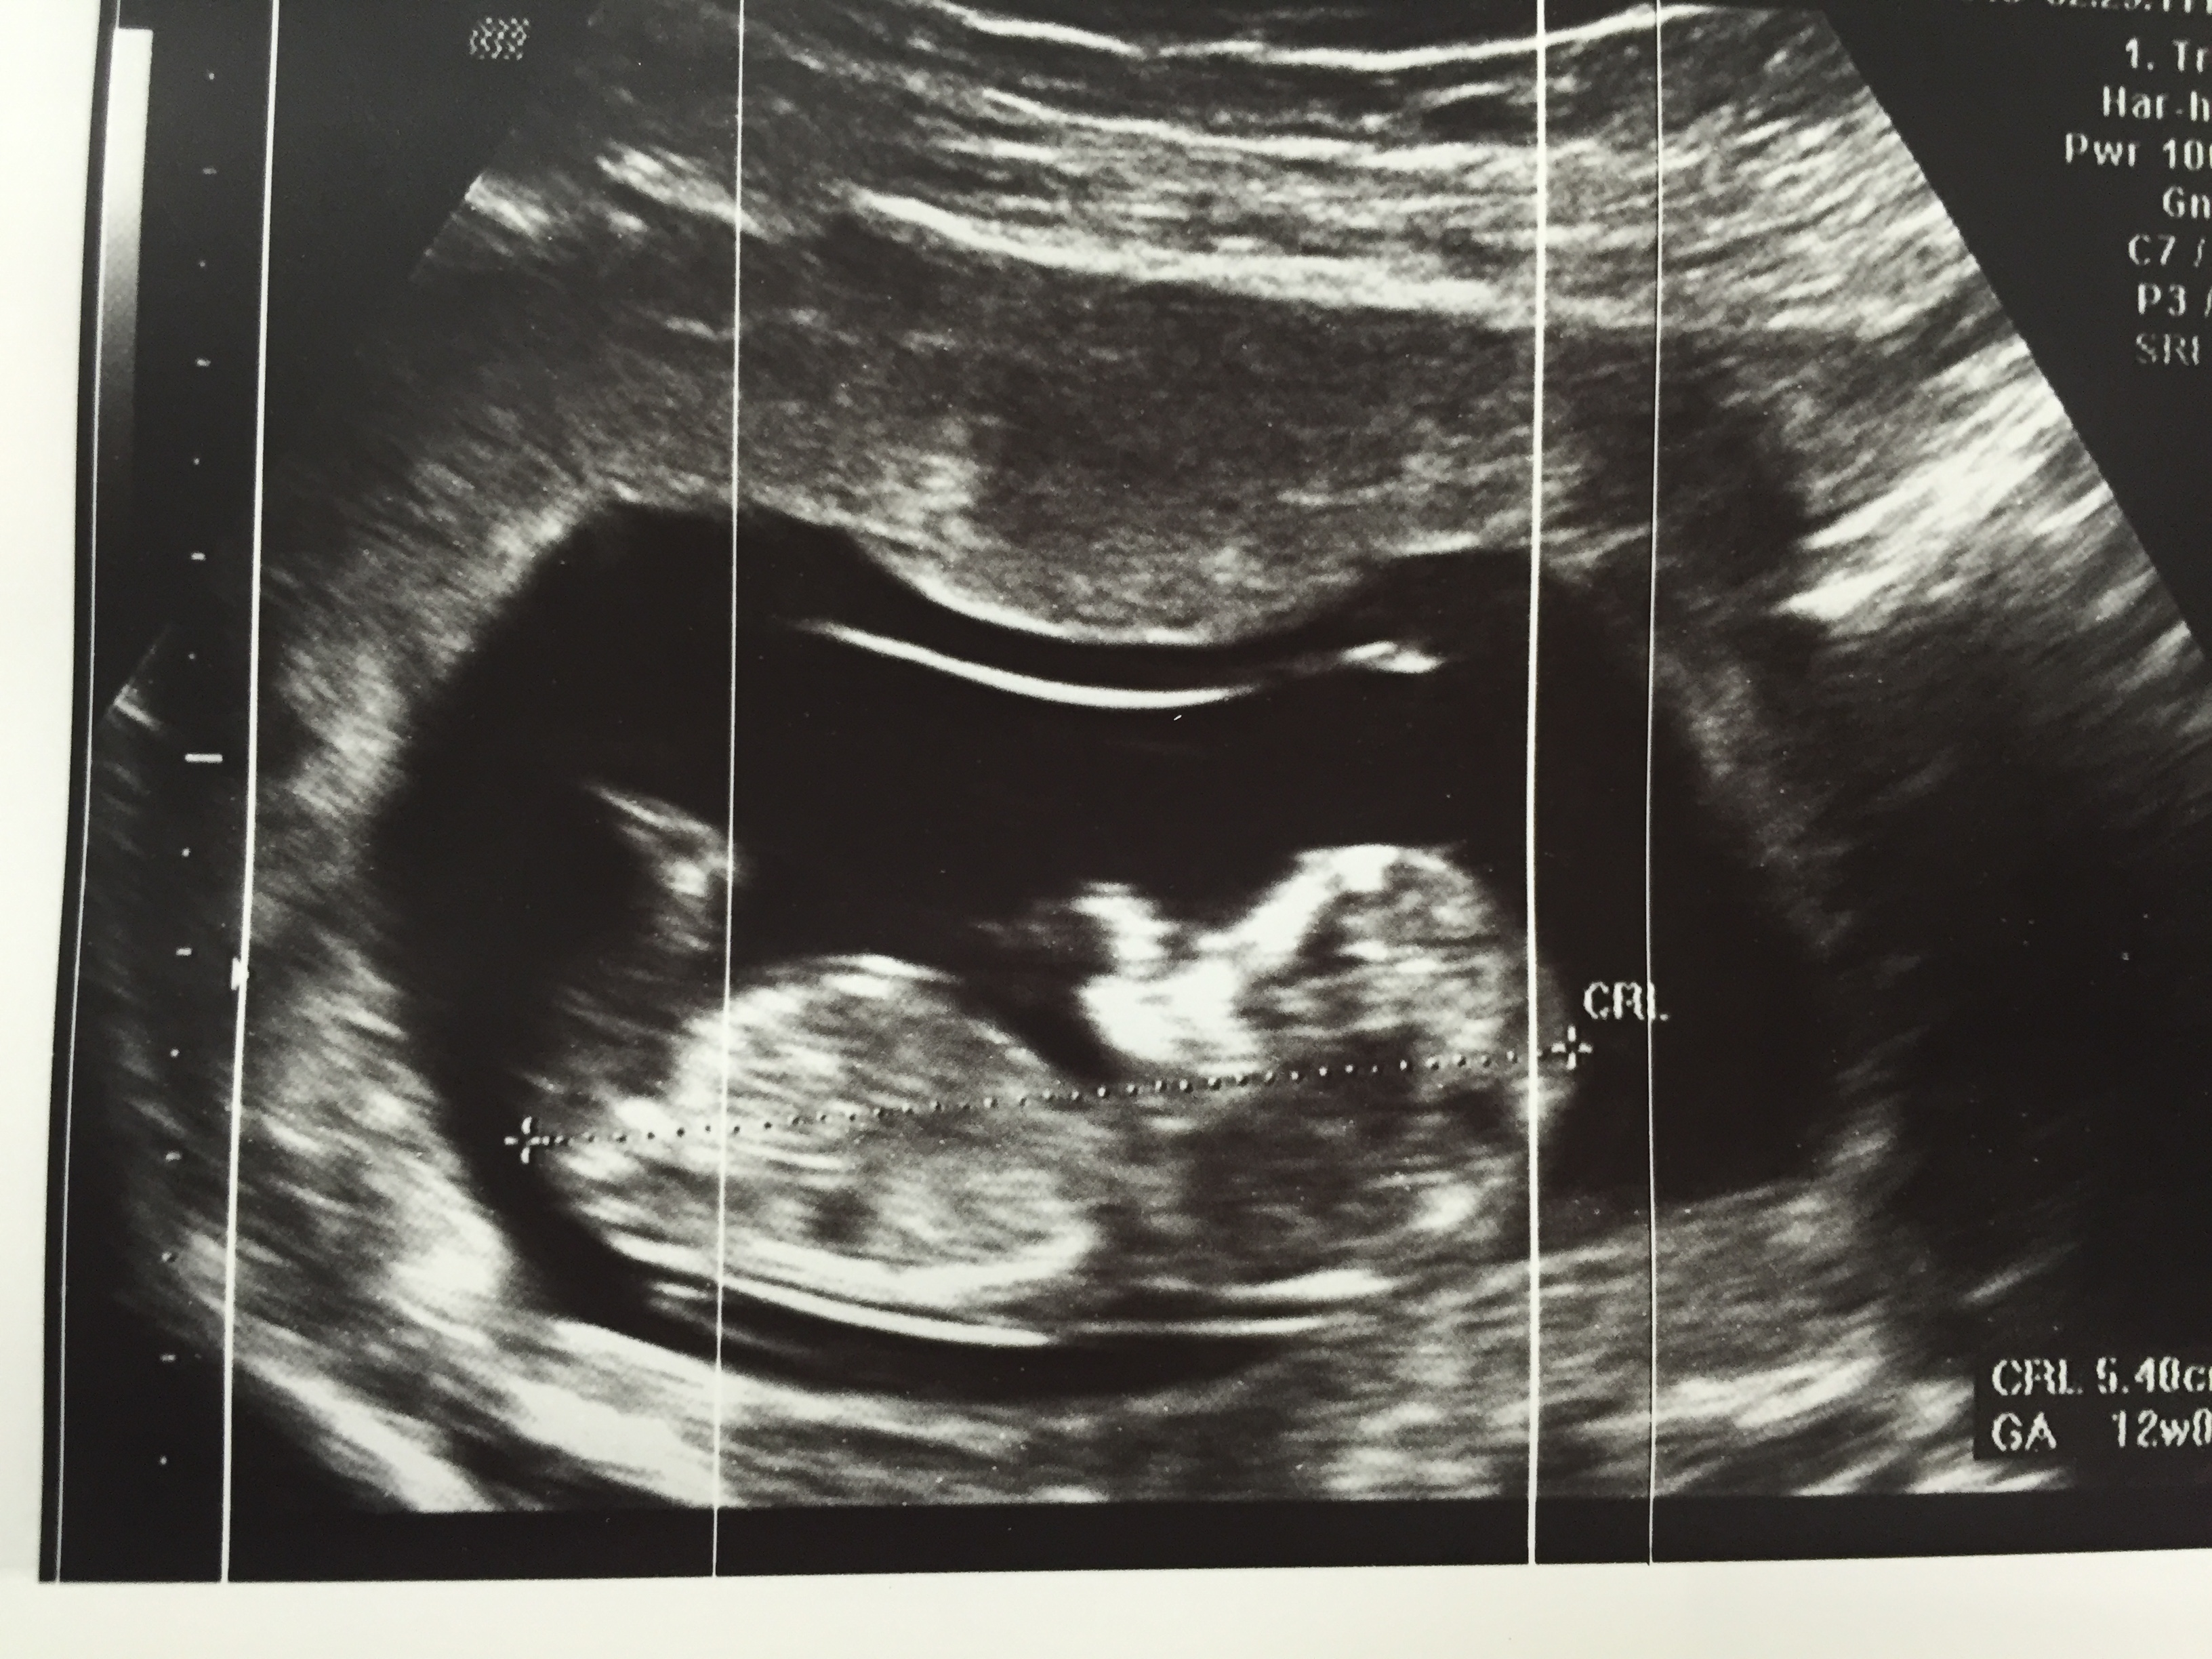

At my 12 weeks ultrasound, doctor advised this is girl. But a lot of inputs the nub look boyish. Anyone have any ideas?Attachment 24016

The nub is VERY distorted from movement. I see why you get boy guesses because it appears at an angle, but its not where it should be its practically coming out of the stomach because of the distortion.

that is indeed the nub but its too high. It should be more where the bottom of your drawn circle is. baby was mid roll or lifting its bottom up and it caused it to be imaged wrong.so you are still at a 50/50.